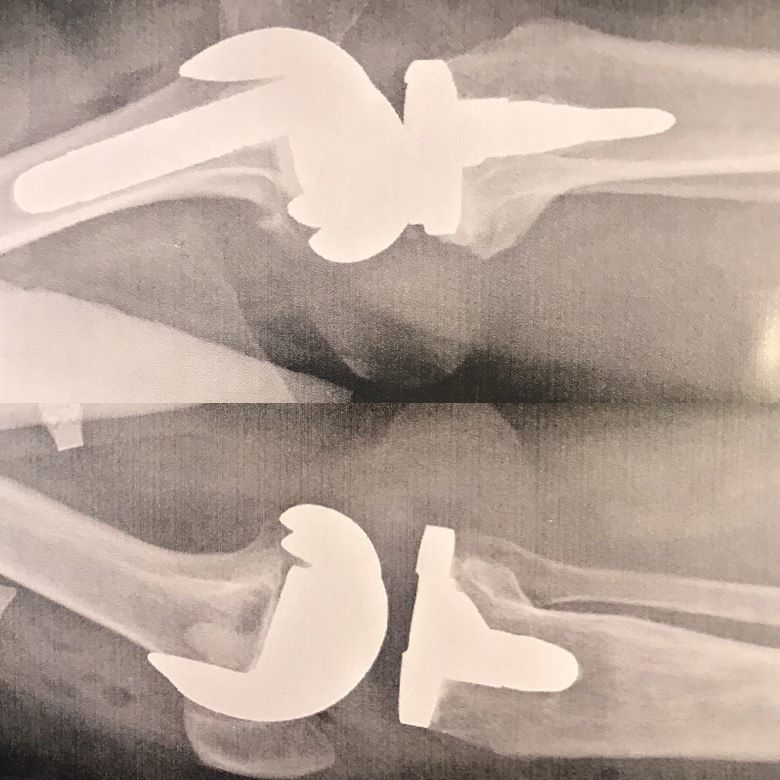

Knee joint replacement

Knee joint replacement is a type of surgery in which an artificial joint or prosthesis replaces the damaged joint.